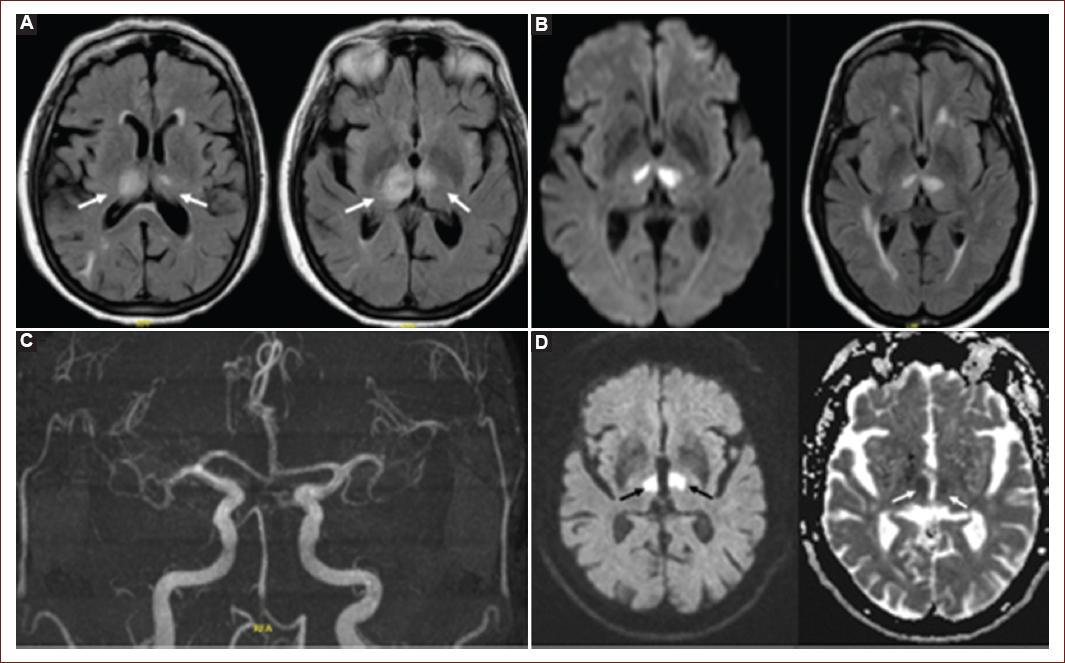

For the diagnosis of bilateral thalamic infarction, non-contrast CT was performed in 82.1% and cerebral MRI in 75%, with both neuroimaging modalities in 60.71% (Fig. 1). The most affected thalamic regions were the bilateral anterior regions in 42.85%, followed by bilateral medial regions in 21.42%. In 17.8% of patients, different regions were affected in the same patient, with one thalamus having anterior involvement and the other complete involvement. Complete bilateral involvement occurred in 7.14% of patients, and only one patient had posterior bilateral involvement (3.57%), while another had medial region involvement (3.57%). The mesencephalon was compromised in 53.5% of patients, and the pons in 1 patient (3.6%).

Figure 1 Bilateral thalamic infarction. A: asymmetric bilateral thalamic hyperintensity on FLAIR sequence. B: bilateral thalamic infarction in brain MRI with Time-of-Flight Angiography. C: percheron artery in MR angiography. D: restricted diffusion area at bilateral paramedian thalamic level with representation in ADC Maps sequence.

During the hyperacute and acute phases, cerebral MRI demonstrates superior diagnostic performance compared to plain head CT for detecting thalamic infarctions. Francioni et al.,22 emphasize the early availability of cerebral MRI with Fluid Attenuation Inversion Recovery and Diffusion Weighted Image sequences, allowing for the diagnosis of hyperacute infarctions. In our series, five patients were diagnosed with head CT, while 23 underwent cerebral MRI or both imaging modalities.

In 12 patients, bilateral thalamic infarction was observed without extension to other vascular structures. Half of these patients exhibited concurrent extension to the mesencephalon. The medial pattern was evident in six patients, five of whom showed mesencephalic involvement. One patient presented pontine involvement with the posterior right thalamus and anterior left thalamus affected, an infrequent occurrence reported in the literature with subsequent fatal outcomes. However, our patient experienced a favorable clinical outcome with a mRs of 2 at 90 days.